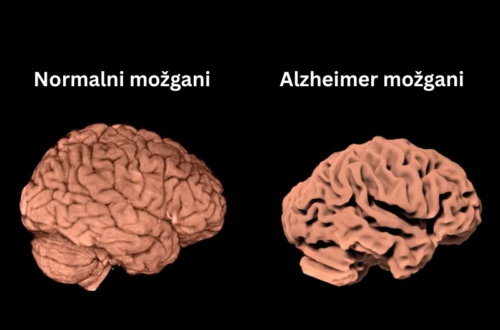

Več magnezija -> večji možgani